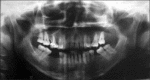

Inflammatory myofibroblastic tumor (IMT) is a rare tumor of uncertain origin with variable biological behavior ranging from reactive lesions to highly aggressive malignancy. Oral IMTs are extremely rare and only 25 cases had been reported so far. A case of IMT with sarcomatous transformation in an extraction site with a history of tooth extraction following tooth mobility of an upper left molar tooth is presented here. The tooth was extracted following a complaint of gingival swelling and mobility of tooth. Though malignant transformation in IMTs had been documented in the extra oral sites, wide search of associated literature suggests, this is the first case of oral IMT showing malignant change associated with gingiva. The case report attempts to highlight the variant possibilities of tooth mobility other than periodontitis and the importance of assessing the primary cause of such conditions.